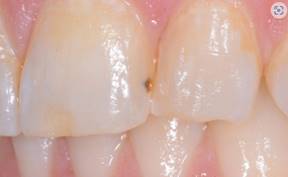

2. Blemishes on the restoration caused by bubbles

When a bubble leaves a divot on the surface of a composite, blemishes with embarrassing discoloration can occur.

A small bubble in the composite has significant stain that the patient complained about, and in fact was the reason they left their previous dentist.